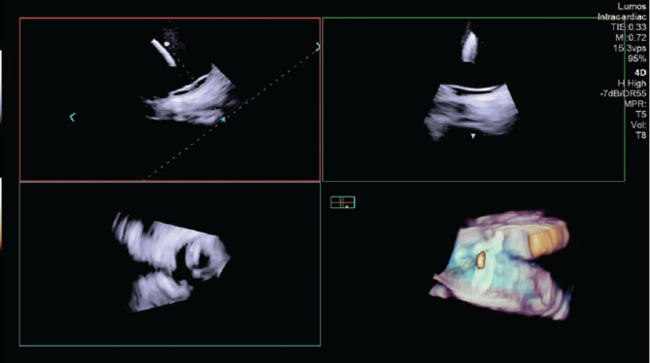

The catheter-based treatment known as pulsed-field ablation (PFA) is emerging as an innovative method of ablation for the treatment of atrial fibrillation. It creates precisely demarcated cardiac lesions that preserve tissue architecture; cell death is confirmed by histological evidence of electroporation, which uses electrical fields to increase cell permeability. PFA can be augmented via four-dimensional (4D) intracardiac echocardiography (ICE) to guide catheter placement, verify tissue contact, and evaluate lesion formation. Additionally, 4D ICE may help clinicians assess sufficient energy delivery to intended tissue and minimize the potential for hemolysis, or the rupturing of red blood cells. In this case, 4D ICE (AcuNav Lumos 4D ICE catheter, Siemens Healthineers) was used to perform PFA and provided detailed views of cardiac anatomy and visualization of tissue contact in multiple planes (Figures 1-2). AcuNav Lumos 4D ICE also guided the transseptal puncture and tenting with visualization of left atrial appendage in the far field (Figure 3) to confirm absence of thrombus.